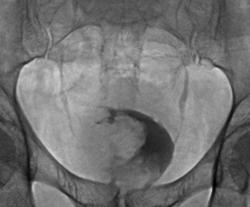

Фрагменты рентгенограмм с увеличение изображения мочевого пузыря.

Да. опухоль мочевого пузыря весьма больших размеров и занимает по всей видимости не менее 3/ объёма мочевого пузыря.